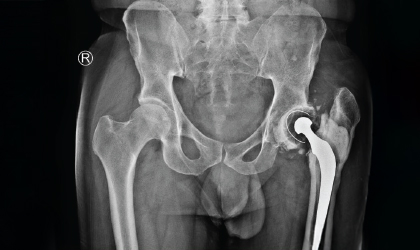

This 62 year old driver travelled all the way from his home in Wayanad to have the hip revised. He had his left hip done in Chennai some 30 years ago. He had shortening and pain. As expected he was very apprehensive before surgery. He recovered rapidly and by 3 months he went back as a driver with legs the same length and painfree

The patient presented with a painful and shortened left leg following a decades-old hip replacement. Understandably, he was apprehensive about undergoing surgery again.

He recovered rapidly, and within three months, he returned to work as a driver. His legs are now of equal length, and he remains pain-free and confident in his mobility.